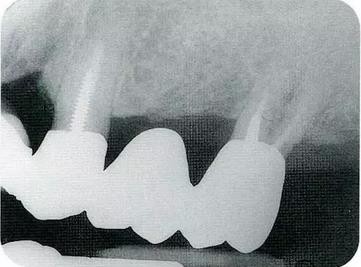

圖20-1術前X光片

360截圖20170120171213911.jpg圖20-8最終修復完成經過了12年后。